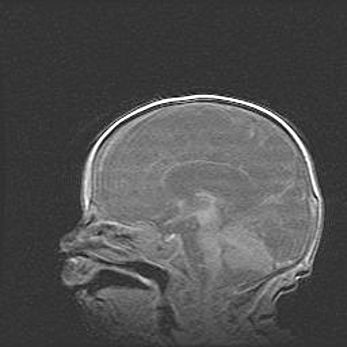

Наружная гидроцефалия с возможной атрофией височных областей.

Возраст: 28 дней

Вес: 3670 г

Пол: мужской

Окружность головы: 38 см

Срок гестации: 40 недель

Гидроцефалия головного мозга у новорожденных – это заболевание, которое характеризуется скоплением избыточного количества спинномозговой жидкости в желудочковой системе головного мозга в результате затруднения её перемещения от места выработки к месту поглощения в кровеносную систему или вследствие нарушения абсорбции. При открытой наружной форме гидроцефалии у новорожденных расширяются и переполняются субарахноидные пространства.

При нормотензивных  формах,  которые,  как  правило,  являются  следствием  перенесенных ишемических  повреждений  паренхимы  мозга,  возможно  сочетание микроцефалии  с нормотензивной гидроцефалией. В основе данных изменений лежит атрофия больших полушарий с преимущественной  локализацией  в  лобно-височных  областях.